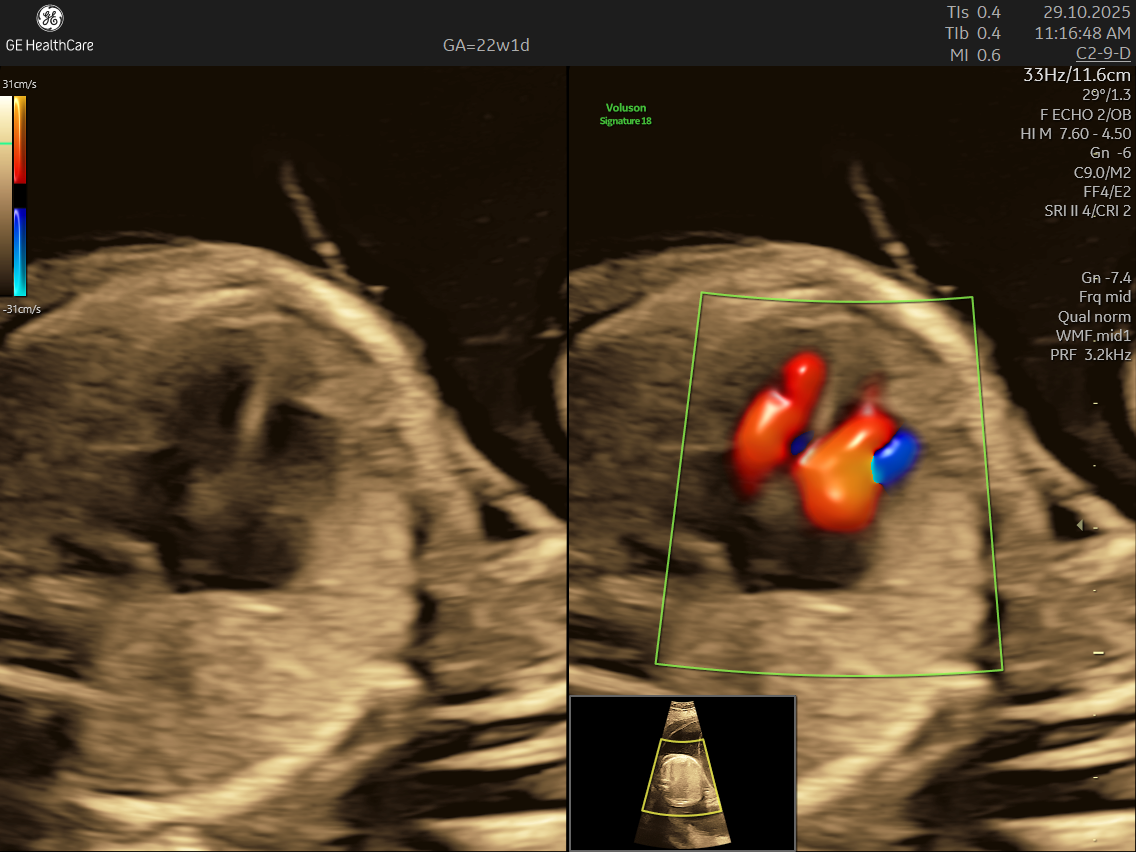

- High Detail: Utilizing advanced Doppler ultrasound technology, it tracks blood movement through the heart and valves, highlighting issues that general scans often cannot detect.

- Blood Flow Patterns: Detects arrhythmias or irregular heartbeats and checks for efficient circulation through the heart and major vessels.

- Transposition of the great arteries, where the aorta and pulmonary artery are switched.

- Abnormalities in blood flow patterns and valve function observed on Doppler imaging.

- Using the advanced GE Voluson S10 ultrasound machine—renowned for its superior imaging clarity, 4D real-time visualization, and automated analysis tools that significantly increase diagnostic accuracy and reduce the chances of missing subtle heart defects.

- Its a specialized ultrasound done between 18–24 weeks of Gestational Age that evaluates the structure, function, and rhythm of a baby’s heart while still in the womb. This scan uses high-frequency sound waves to create detailed images of the fetal heart, aiding in the detection of congenital heart defects (CHDs) and other abnormalities.